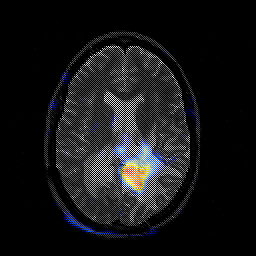

Glioblastoma multiforme overlay -- Slice #31

[Home][Help][Clinical][Tour 1][Tour 2][Tour 3] Slice 31